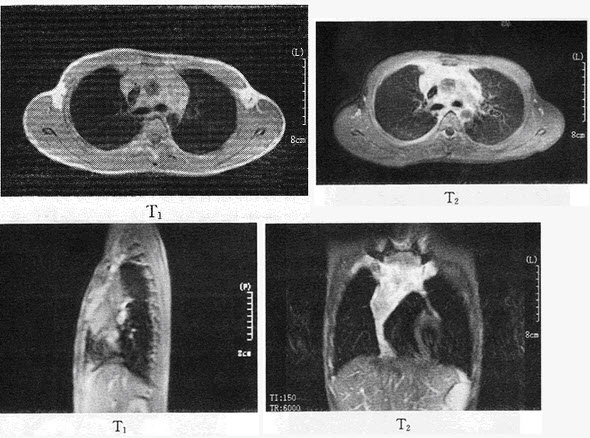

105������ѡ���� �����У�63�ꡣ��"�ر�����ʹ3�����࣬����1��"��Ժ���ز�CTʾ�����Ϸ�ռλ�Բ��䣬�ݸ��ܰͽ��״����࣬T9��T10������ƻ�����ά֧���ܾ������Ϸ�Ҷ֧���ܴ�����������ʾ���ͷֻ��ٰ�����ECTʾ��T9��T10��L1���Ҳ��5�߹�ת���Բ��䡣ͷMRI������B����δ�����쳣��

������3���º�ͻ��һ��֫�左��״������Ҫ���ǽ��еļ���ǣ���

A.ͷMRI�����˽�������ת��

B.����MRI�����˽�������ת��

C.����CT�����˽�����ת��

D.Ѫ������飬���˽�����Ѫ֢�ȵ�����쳣

E.��ʱ����Ҫ��飬�۲첡��仯